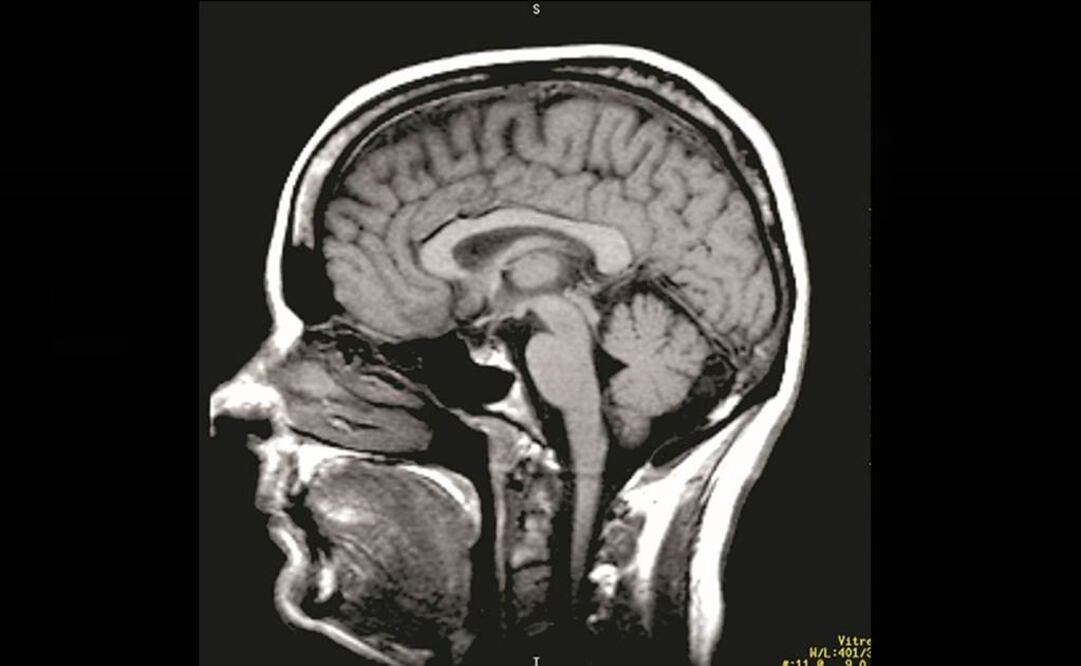

"El cerebro siempre está trabajando, aunque estés sentado sin hacer nada, y puede ser enseñado para actuar en nuestro beneficio", aseguró el físico teórico Jyri Kuusela, que trabaja para la Agencia Espacial Europea (ESA) e impulsa en España la implantación del "neurofeedback".

Creencias populares como que usamos sólo un porcentaje ínfimo del verdadero potencial cerebral "son falsas, porque este órgano trabaja continuamente, guardando o descartando información, evaluando y haciendo su propio mantenimiento", afirmó este científico finlandés.

El cerebro humano procesa diariamente unos 60 mil pensamientos, de los cuales el 94% se repiten y el 80% son negativos pero "un entrenamiento con técnicas de 'neurofeedback'" o retroalimentación neuronal permite cambiar su funcionamiento a nivel inconsciente", dijo.

El tratamiento es "sencillo y personalizado y pasa por monitorizar la actividad cerebral a partir de EEG interactuando con la propia persona, de manera que es como si el cerebro se pudiera ver a sí mismo ejecutando su actividad".

A partir de ahí, se puede estimular al cerebro hasta su autorregulación ajustando sus diferentes frecuencias, desde los ritmos Beta altos y bajos en los que la persona se encuentra en alerta o tensión, hasta los Delta del sueño profundo e incluso más allá, en los Infrabajos.